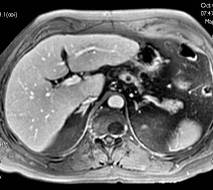

Recherche de métastases dans le bilan d'un adénocarcinome du colon. Pas de métastases visibles mais aspect de cirrhose hépatique, diagnostic confirmé ultérieurement par l'histologie